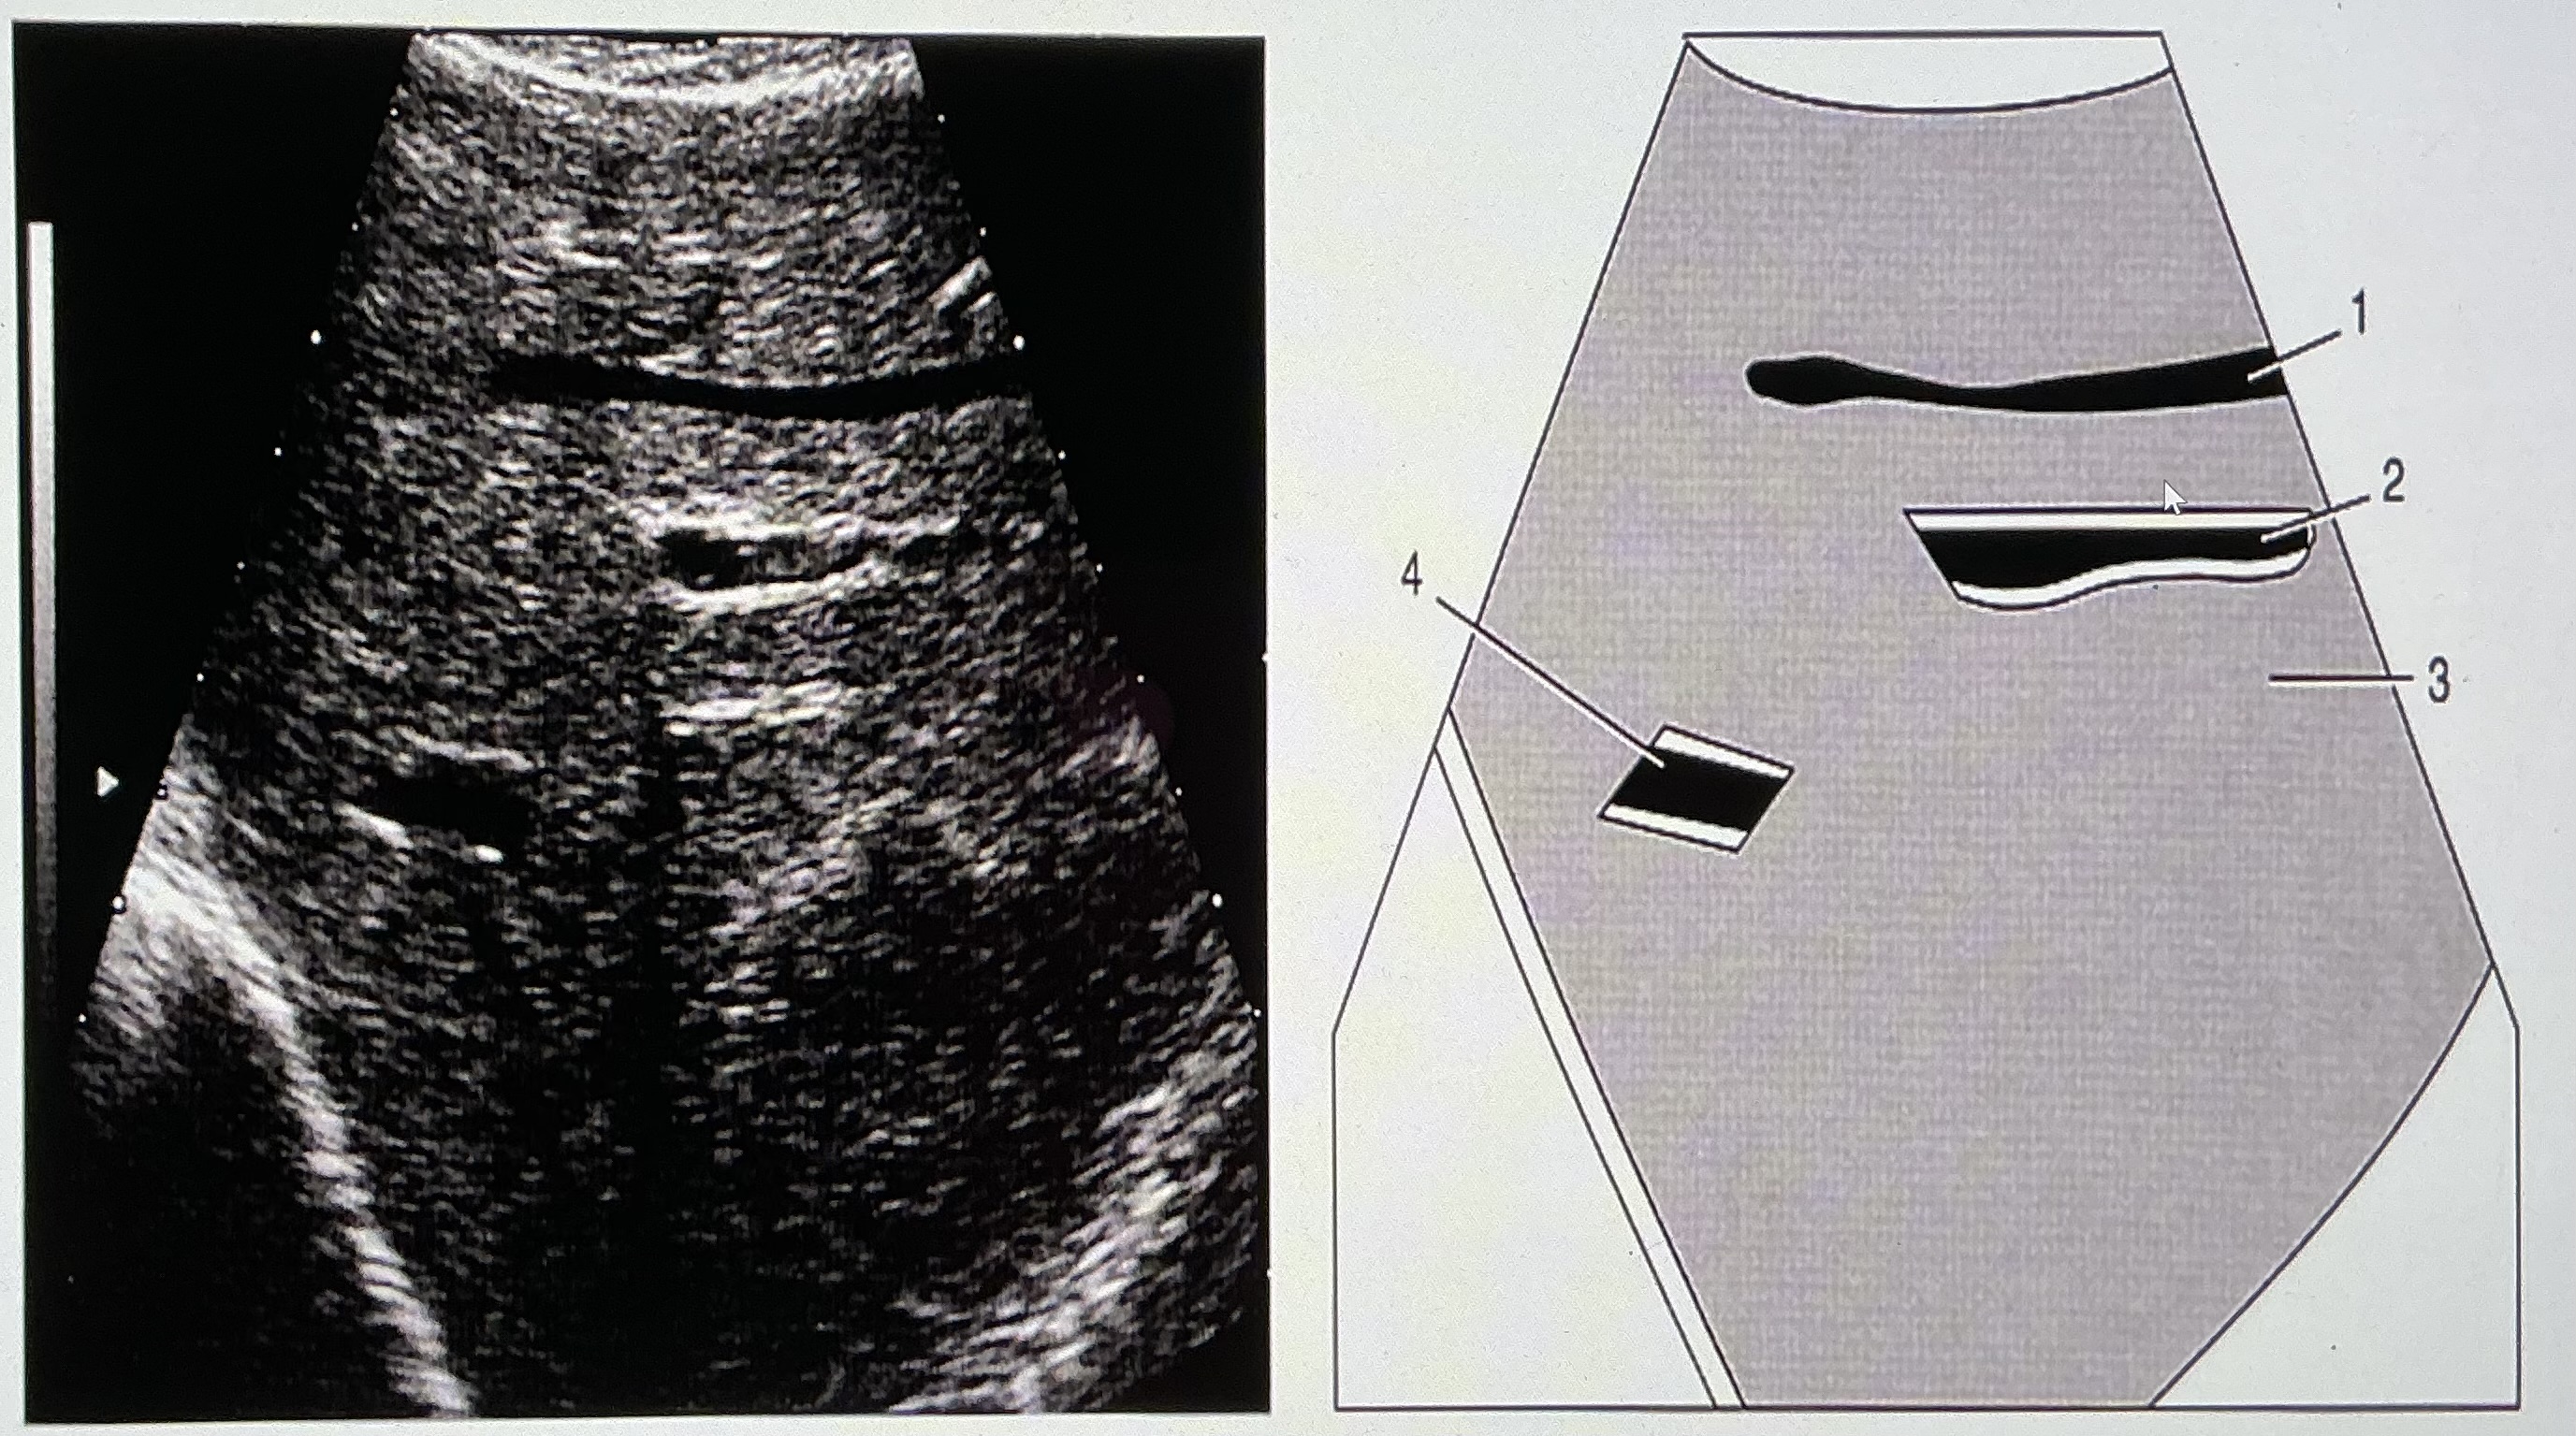

#1 Indicates

none of the above

#2 indicates

thoracic aorta

#3 refers to the rectus abdominus muscle

false

On the diagram, what do numbers 3 and 4 refer to?

medial and lateral branches of the left portal vein

What do #6 and @7 refer to?

splenic vein and IMV

Which numbers on the diagram/image indicate portal venous structures?

2 and 4